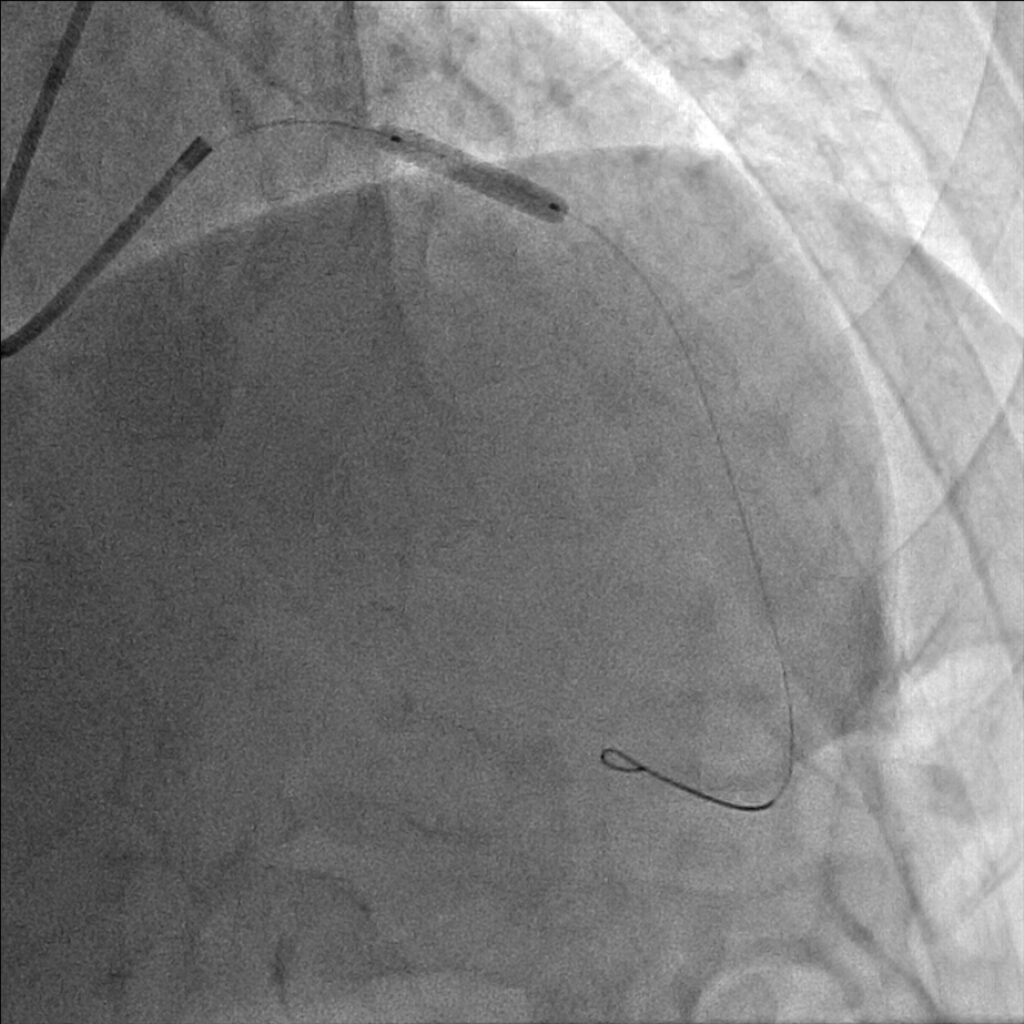

妻の勧めで近所の医院を受診しました。安静時心電図検査では何の異常もなかったのですが、念のためにと私の外来を紹介されました。ベルトコンベアーの上を歩く運動負荷心電図検査でいつもと同じような症状を覚え、心電図に異常が出現しました。私は労作性狭心症と診断しました。手首からカテーテルを挿入した冠動脈造影検査で、一番大きな冠動脈枝の近位部に高度な狭窄が見つかりました。後日、風船とステントを用い、狭窄を開大しました。症状は完全に消失し、今は農作業に精を出しています。

治療はカテーテルを使い風船やステントで狭窄部を拡張し、血液の流れをよくすることが一般的です。冠動脈の全ての枝に狭窄がある方、あるいは左主幹部と呼ばれる最も太い血管と他の枝に病気が重複している重症な方等には冠動脈バイパス手術をお勧めしています。しかし、症状が無い方や心筋虚血を心電図等で客観的に認めない方は、冠動脈に狭窄があっても、こうした治療をせず悪玉コレステロールを下げる、高血圧をコントロールする、禁煙をする、糖尿病のコントロール等の冠動脈硬化の危険因子を治療することで経過をみることも多いです。